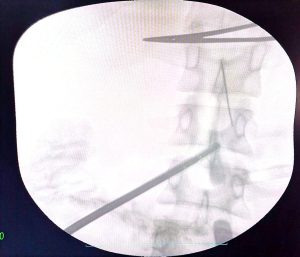

كان المستشفى الرئيسي قد استقبل فتاة تبلغ من العمر ٣٠ عاما، تعاني من آلام حادة ومزمنة بالبطن، ومن خلال تقصي التاريخ المرضي، تبين أنها ابتلعت إبرة خياطة عن طريق الخطأ منذ ما يقرب من ٤٠ يوماً، وعلى الفور، تم إجراء الفحوصات اللازمة والأشعة المقطعية التي أظهرت أن الإبرة لم تكتفِ باختراق جدار المعدة، بل استقرت في موقع تشريحي دقيق جداً بجوار الشريان الكبدي والوريد البابي الكبدي.

وقام الفريق الطبي الذي ضم كل من، الدكتور محمود حسب النبي، أستاذ مساعد بقسم الجراحة، والطبيب حماده فتحي، والطبيب خالد حسان، والطبيب حسام محمود، مدرسين مساعدين بالقسم، والطبيب ماريو أيوب طبيب مقيم بالقسم، ومن قسم الأشعة التشخيصية والتدخلية، فريق طبي تحت إشراف الدكتور حسن مجلي، رئيس القسم، وضم كل من الدكتور حمدي إبراهيم، أستاذ مساعد بقسم الأشعة التشخيصية، والطبيب ميرنا يوسف، مدرس مساعد بالقسم، يعاونهم فريق طبي من قسم التخدير جاء تحت إشراف الدكتورة هالة سعد، رئيس القسم، وضم كل من الدكتور جورج مجدي، مدرس بالقسم، والطبيب أمونيوس خليل، مدرس مساعد بالقسم، كما عاونهم أماني أحمد، تمريض بقسم الجراحة، وحسن علي، فني الأشعة، باستخدام جهاز الأشعة C-Arm، بدلاً من اللجوء إلى الجراحة التقليدية (فتح البطن الاستكشافي)، التي تتطلب وقتاً أطول للتعافي، لرصد مكان الإبرة بدقة متناهية.

ونجح الفريق الطبي في استخراج الإبرة بالكامل باستخدام المنظار الجراحي عبر (٣) فتحات صغيرة فقط في جدار البطن.